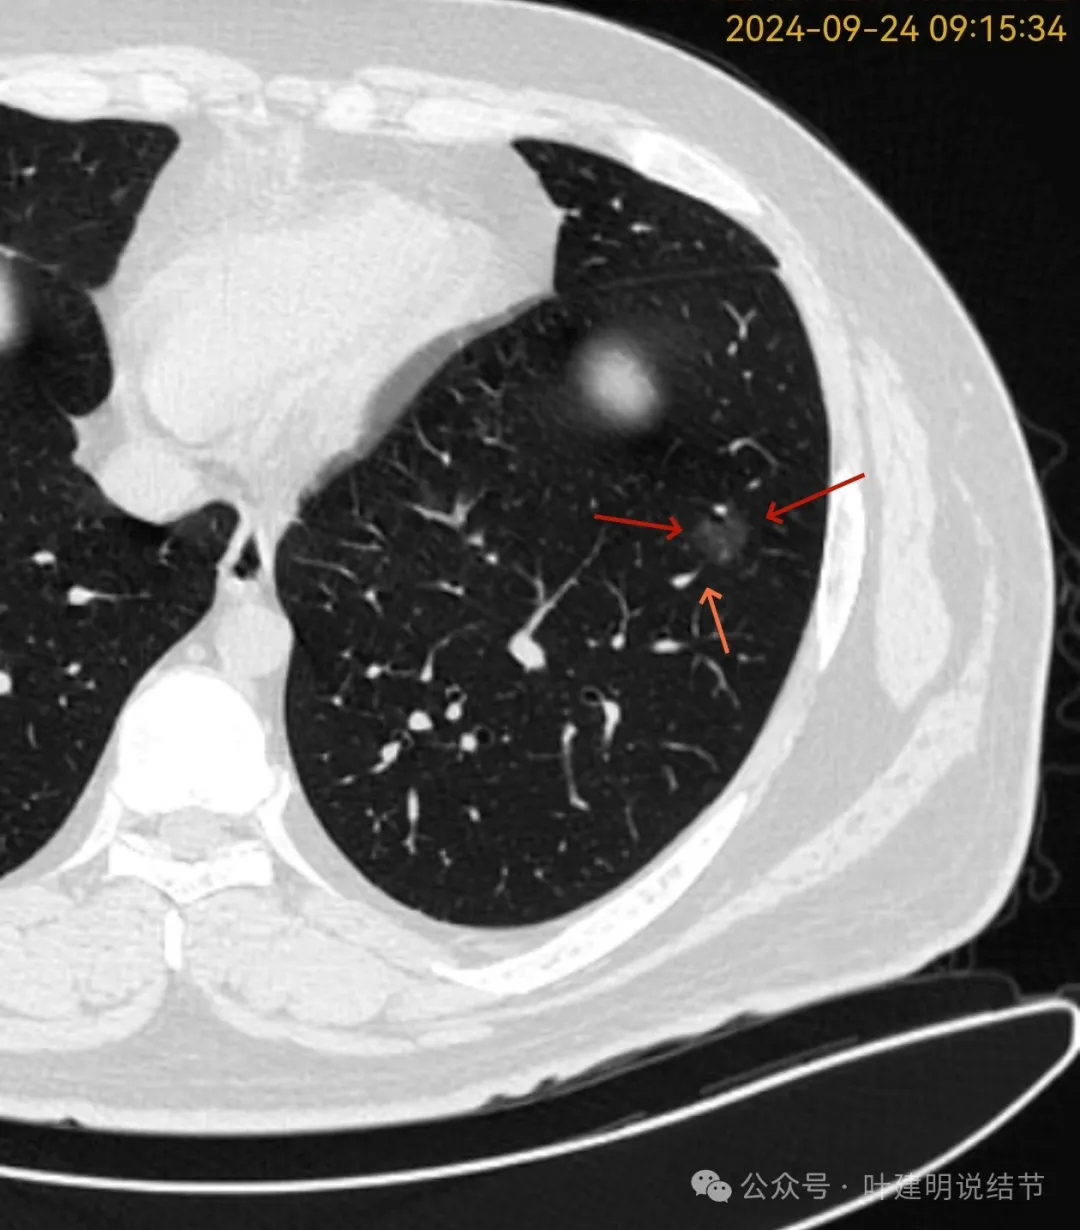

再看2024年9月复查的片子:

有少许偏实性成分,整体轮廓清。

纯磨密度,不太纯,血管贴边,血管与病灶间隙消失,整体轮廓与瘤肺边界清。

血管弯征可见、细毛刺明显、细支气管扩张,血管进入。